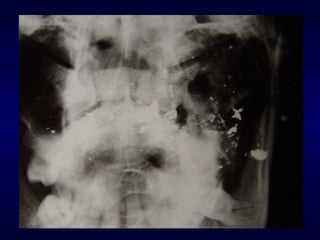

FERIDAS POR ARMA DE FOGO  (FAF) TRATAMENTO: controle da hemorragia suturas após limpeza do ferimento suturar de “dentro  para  fora” (reduzir  fraturas e depois fechar tecidos moles) perda de substância tecidual Retirada dos projéteis: risco x benefício “ quando uma bala para de se mover, para de causar dano”

CORPOS ESTRANHOS dentes fragmentos ósseos vidro pedras  roupa  terra  madeira materiais restauradores

CORPOS ESTRANHOS TRATAMENTO: Remover corpo estranho para evitar infecção e atraso na cicatrização Antibioticoterapia até que a cicatrização primária tenha terminado Profilaxia do tétano